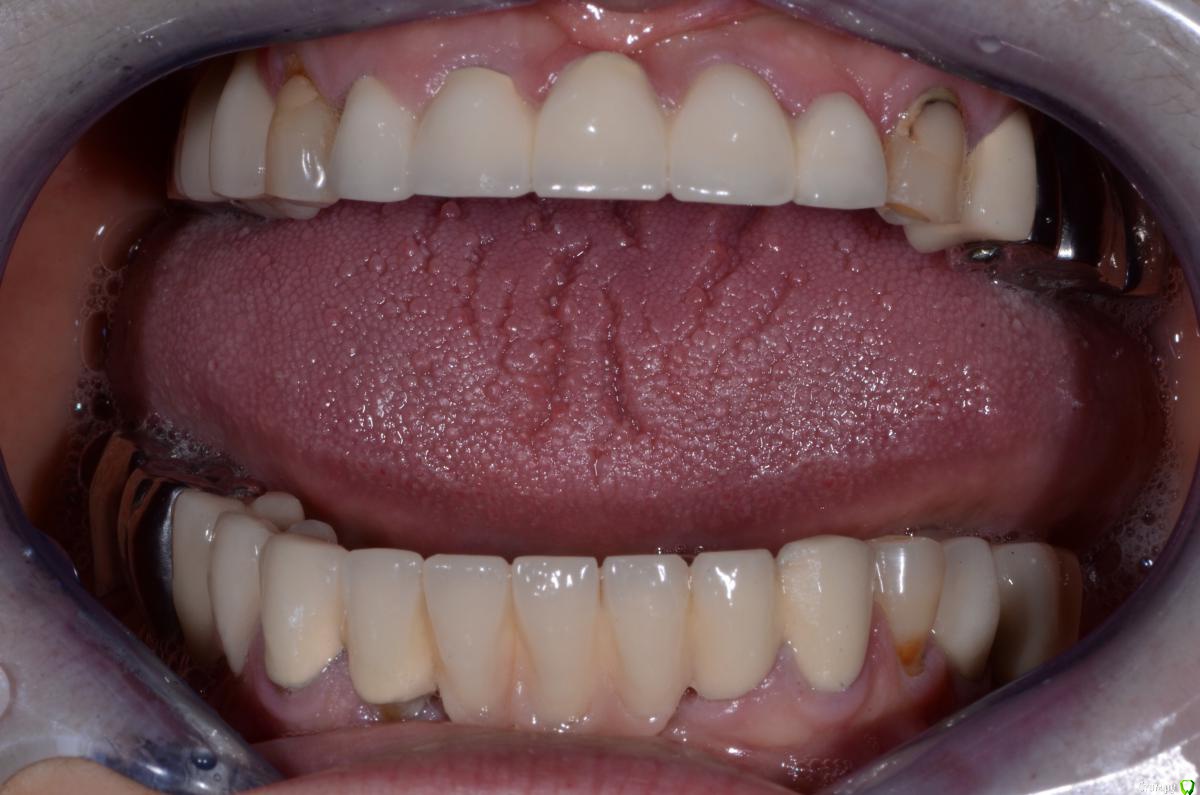

DimaKoleso Опубликовано 24 января, 2016 Поделиться Опубликовано 24 января, 2016 Доктора, вот такая пациентка пришла. Что бы вы сделали? Ссылка на комментарий

DimaKoleso Опубликовано 24 января, 2016 Автор Поделиться Опубликовано 24 января, 2016 Пациентка хочет все белое и верх и низ Ссылка на комментарий